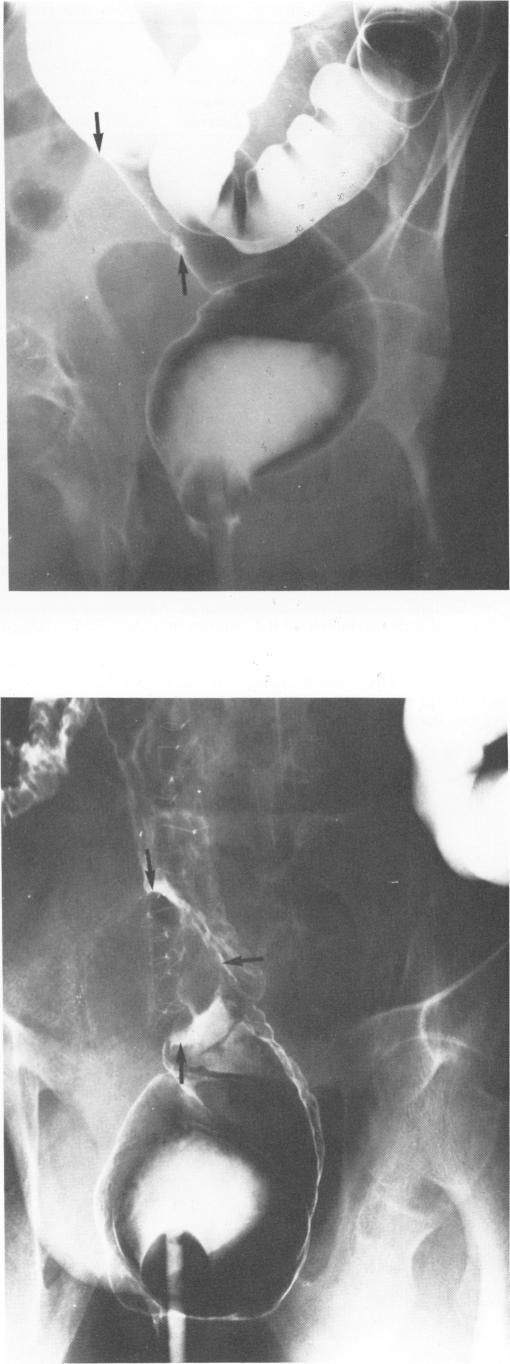

Twenty-seven carcinomas of the colon or rectum are presented which could retrospectively be measured on radiographs at two separate occasions. The mean diameter of the tumors at first and second investigations was 35 mm (10-90 mm) and 65 mm (30-110 mm), respectively, and the median interval between these examinations was 11 months (4-91 months). The median linear growth rate was 0.083 mm/day (0.008-0.262 mm/day). The median time for doubling of tumor volume was 130 days (53-1570 days), assuming a three-dimensional pattern of tumor growth. A significant correlation between poor differentiation and high linear growth rate (greater than or equal to 0.1 mm/day) was found. It is suggested that the high growth rate observed in this investigation in comparison with some previous studies may be due to the large size of the tumors and, hence, to their great risk of being malignant already at the first examination.

本文呈现了27例结肠或直肠癌病例,这些病例可在回顾性研究中于两个不同时间点通过X光片进行测量。首次和第二次检查时肿瘤的平均直径分别为35毫米(10 - 90毫米)和65毫米(30 - 110毫米),两次检查之间的中位间隔时间为11个月(4 - 91个月)。中位线性生长速率为0.083毫米/天(0.008 - 0.262毫米/天)。假设肿瘤呈三维生长模式,肿瘤体积翻倍的中位时间为130天(53 - 1570天)。研究发现,低分化与高线生长速率(大于或等于0.1毫米/天)之间存在显著相关性。有人提出,与之前的一些研究相比,本研究中观察到的高生长速率可能是由于肿瘤体积较大,因此在首次检查时就已经具有较高的恶性风险。